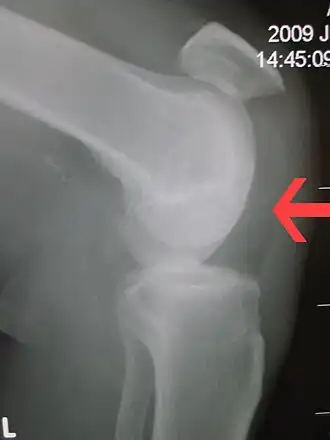

| Ruptura do tendão patelar mostrando uma distância marcada entre a tuberosidade tibial e a parte inferior da rótula do joelho. | |